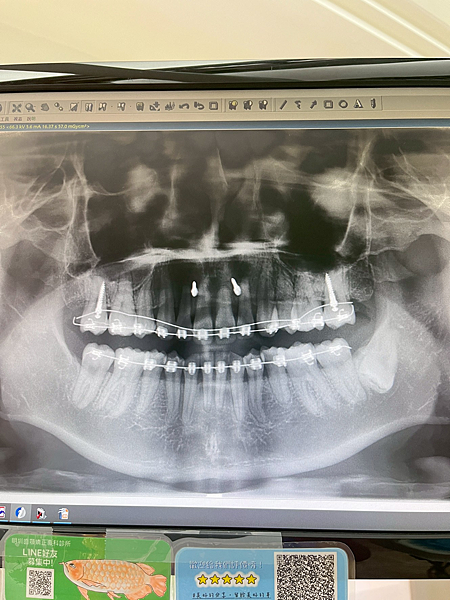

2023/01/05這次要釘骨釘拉 第一次打骨釘其實滿緊張的,但其實沒想像的恐怖,速度很快,反而是醫生的清潔教學講很久XDDD

2023/2/14今天把上排牙齒透過骨釘往上拉,感覺快大功告成啦不過刷牙真的非常難刷,超容易卡東西的

2023/06/29 這次牙醫告訴我要在門牙上再打兩根骨釘,這樣門牙網上的移動才會在更快一點

2023/07/18 今天的們診是打門牙上面的骨釘,剛打完麻藥退的時候真的超級痛!!!!! 然後 我就吃很多冰XDDDD

其實隔天就好多了,醫生幫我打在很上面,所以比較不會有異物感

2023/08/08 今天開始用門牙上的骨釘拉牙齒,加上拍矯正中的照片,覺得牙齒整齊很多,目前還需要往上移動